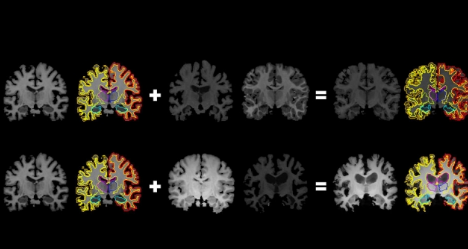

麻省理工学院的研究人员开发了一种系统,该系统可以从未标记的数据中收集更多的标记训练数据,这可以帮助机器学习模型更好地检测与神经系统疾病相关的大脑扫描中的结构模式。该系统了解未标记扫描的结构和外观变化,并使用该信息将一个标记扫描塑造和塑造为成千上万个新的,不同的标记扫描。图片由研究人员提供

在生成新扫描时,系统将随机流场应用于原始标记的扫描,该扫描流围绕体素移动,直到结构上与真实的未标记扫描相匹配。然后,它覆盖了随机强度转换。最后,系统通过遵循体素在流场中的移动方式将标签映射到新结构。最后,合成扫描与真实的,未标记的扫描非常相似,但是具有准确的标记。